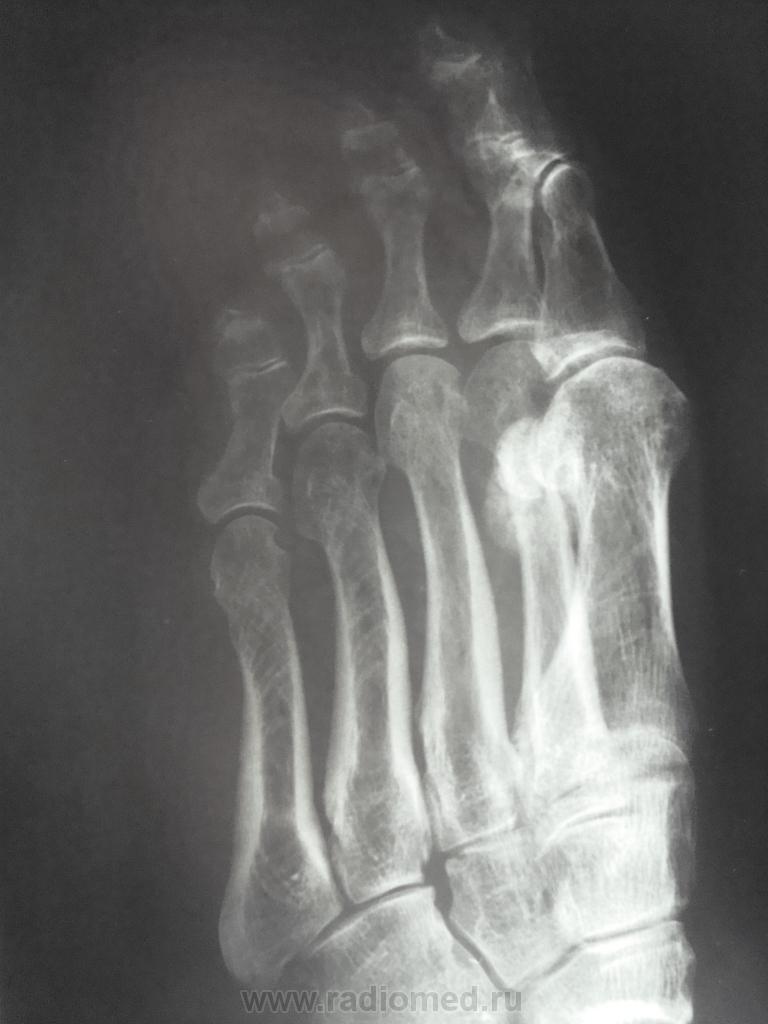

женщина обратилась с жалобами к участковому терапевту на боли во 2 и 3 пальцах правой стопы, предварительный диагноз у них как всегда " артроз", про травму ничего не пишут в амбулаторной карте, как внешне выглядит стопа тоже не описывают. Может ли это быть патологическим переломом????

Перелом по типу маршевого, но так как на фоне минералопении - это ближе к Лоозера, чем Дойчлендера...

Боюсь прослыть упрямым ... Но все-таки... Дружный DS б-ни Дойчлендера выставлен только на основании утверждения, что травмы не было. Я тут "посоветовался" с С.А.Рейнбергом. Он утверждает, что отличительной особенностью полоски просветления при б.Д. является ее ровность, прямолинейность. При переломах полоска зигзагообразная, что мы и имеем. На фоне остеопении больная могла просто наступить на камень и этого не заметить. Вот вам и перелом.

На рентгенограммах выявляется локальная периостальная реакция в виде одно- или многослойного периостоза. Соответственно ему в костномозговом канале появляется склероз, сужающий просвет канала. В кортикальном слое и среди склероза видна полоска просветления, чаще имеющая клиновидную форму- собственно « ползучий » перелом. При продолжении действии нагрузки он постепенно увеличивается. Однако если травмирующий фактор прекращает свое действие, достаточно быстро восстанавливается нормальная структура кости.